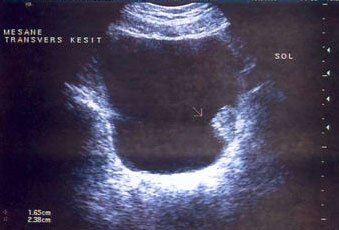

Mesane tümörü tanısı hastanın anamnezi, detaylı fizik muayene, radyolojik görüntüleme ve sistoskopi ile konulmaktadır. Radyolojik görüntüleme de ultrasonografi genellikle yeterli olmaktadır. Ancak bazen başlangıç aşamasında milimetrik boyutlu tümörler ultrasonografide atlanabilmektedir. Klinik şüphe halinde sistoskopi ( mesanenin kamera yardımıyla görüntülenmesi), ilaçlı bilgisaraylı tomografi, idrarda sitoloji bakılması, idrarda tümör markırları değerlendirilmesi (şu an için çok başarılı sonuçlara sahip değil) gerekebilmektedir. Yine ultrasonografik olarak tanı konulmuş olsa dahi tümörün mesane dışında doğru uzanımının ve olası uzak organ yayılımının (metastaz) değerlendirilmesi içinde bilgisayarlı tomografi(BT), magnetik rezonans görüntüleme(MR), pozitron emisyon tomografi (PET) gibi görüntüleme yöntemlerine ihtiyaç duyulabilir. Ancak mesane tümörü kesin tanısı sistoskopi ve eş zamanlı mesaneden biyopsi alınması ile konulur.

Şekil 1: Mesane tümörünün ultrasonografik görüntüsü